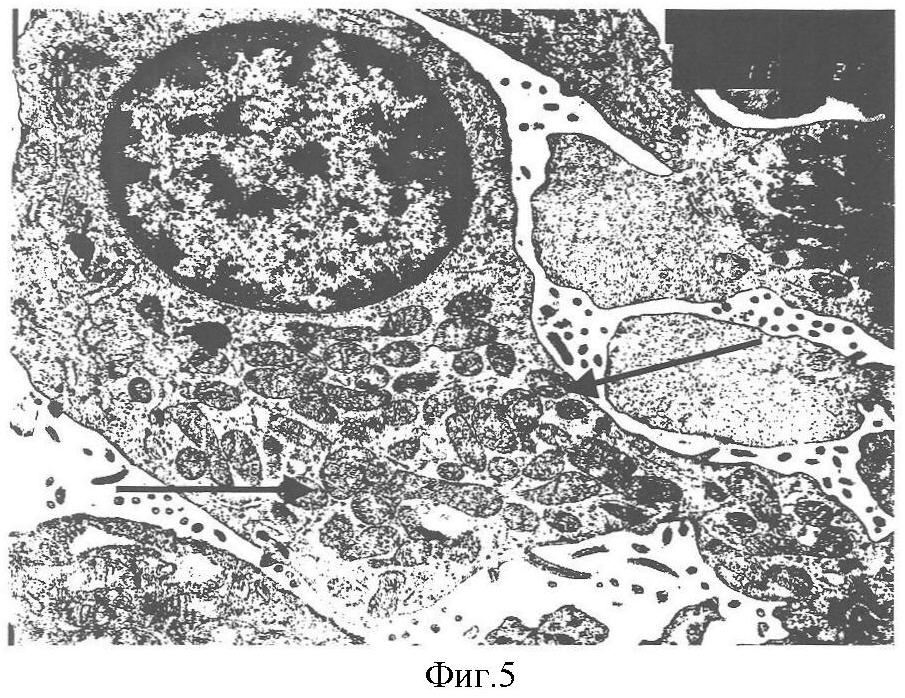

1. В гладкой мышечной ткани мочевых путей (при гидронефрозе у детей, при аденоме простаты у пожилых мужчин и при некоторых других заболеваниях) иногда можно наблюдать такие морфологические изменения: на фоне общего снижения гистохимической активности митохондриальных ферментов видны отдельные миоциты с резко увеличенным содержанием метки. То есть на фоне общего тканевого энергодефицита появляются клетки с резко увеличенным числом митохондрий (та же ситуация, что и в скелетной мышце). Интересно, что у таких больных хирургическое оперативное лечение значительно менее эффективно – коррекция макроскопического дефекта (обструкции или расширения стенки) не приводит к существенному восстановлению функции, так как гладкомышечная ткань функционально дефектна. И в этом отношении также понятно, что адаптационный потенциал митохондриальной пролиферации должен максимально использоваться. Пролиферация митохондрий (стрелки) в нефроцитах у ребенка с инфантильным нефротическим синдромом представлена на фиг.5. Электронная микроскопия. Ув.x20000.

2. То же можно видеть в таких энергозависимых структурах, как почечный эпителий. Авторами обнаружены митохондриальные пролифераты в нефроцитах у детей при различных почечных заболеваниях, характеризующихся функциональной недостаточностью почек, в частности при инфантильном нефротическом синдроме.